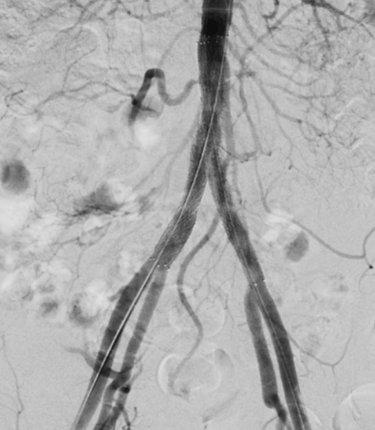

Step 3: Restored Circulation

✔ Improved blood flow

✔ Reduced symptoms

✔ Better tissue health

(Sometimes a stent is placed to keep the artery open.)